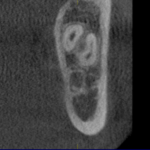

従来のレントゲンは2次元=平面でしか見ることができず、

そのために”奥行き”がわからないという欠点=限界がありました。

新たに導入したデンタルCTでは縦・横に加え奥行きがわかります。

これは画期的なことで、病変部あるいはインプラント治療には

診断不可欠な骨形態を3次元的に把握できるようになります。

それにより、従来よりも飛躍的に多くの情報を得られ、

より正確な診査・診断が可能になりました。